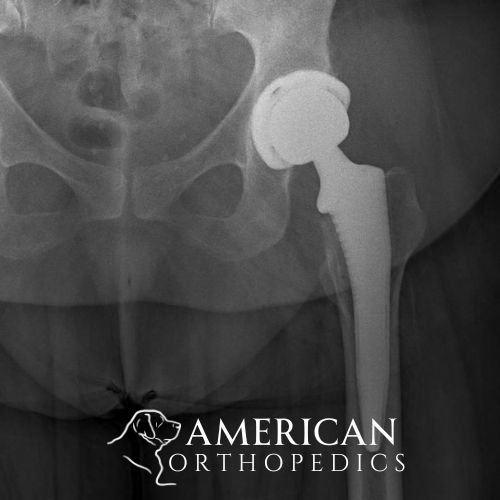

Bilateral Anerior Hip Replacement

Patient of Dr. Ratner.

Right Hip

post op right hip

Left Hip